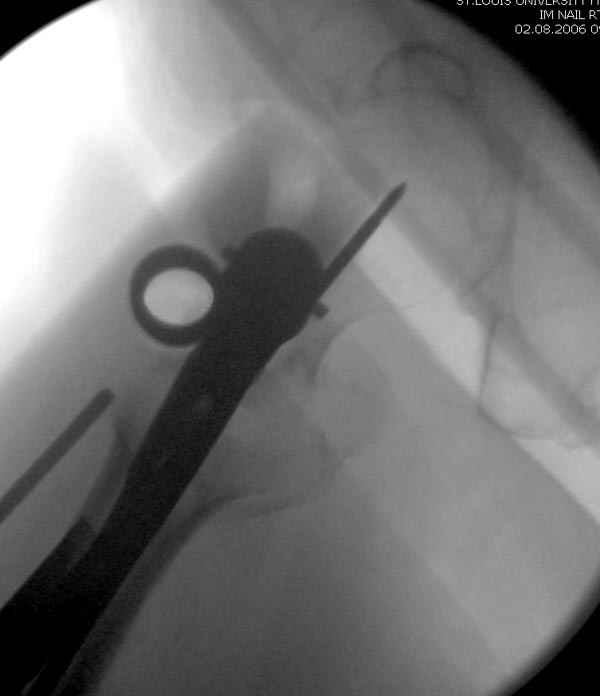

Здесь сканнированные снимки импланта и операционные снимки больной.

На этом снимке процесс компрессии нижним болтом.